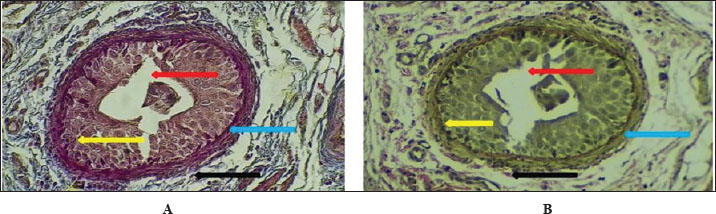

The fundamental unit of kidney structure and function presented in the Introduction was the nephron, which was a combination of the glomerulus, proximal convoluted tubule, loop of Henle, distal convoluted tubule, and collecting duct. When stained with hematoxylin and eosin, the low-power study of Fig. 1 marks off two regions in the kidney: the cortex on the outside and the medulla on the inside. The thin connective tissue capsule encompasses the cortical area on the outside of the structure (at the blue arrow). The renal cortex holds renal corpuscles and some tubules, but the interior appears mostly tubular because it consists of Henle collecting ducts and loops. One can observe renal corpuscles, which are marked by visible Bowman’s capsules, as indicated by a yellow arrow. In Figure 2, Alcian blue staining shows the renal cortex in the 40x section and proximal and distal convoluted tubules. The simple cuboidal epithelium (indicated by red arrows) on the tubules is a special feature of early postnatal development. Near the corpuscle, glomerular arterioles (blue arrows) grow to aid blood circulation. Using the Alcian stain, glycosaminoglycans located in basement membranes and the extracellular matrix are visualized, and this helps make epithelial cells more noticeable. In Figure 3, the Masson’s Trichrome-stained picture at 10x showed how the kidney’s connective tissue is organized. A thin layer (marked with the red arrow) made of fibers surrounds the organ, giving the tissue a blue-green color because of the collagen. In Figure 4, the section from the 1-week shows images of both H&E staining and Alcian blue staining of the ureter cross-sections. The ureteral lumen is small throughout and runs in the center (pictured by the red arrow). On the inside, there was a small layer of squamous epithelial cells (yellow arrows) and a thin layer of muscle envelope (blue arrows) essential for making urine flow. Alcian blue mucopolysaccharides were found in the epithelium and the space below, suggesting that the mucosa was developing at the beginning of the week. In Figure 5, two 40x showed the ureter stained with PAS and Masson’s Trichrome. The yellow arrow shows the epithelial layer, the blue arrows show circular smooth muscle fibers, and the red arrow shows the longitudinal muscle layer. The outer layer is indicated by the black arrow. The Masson stain in panel B highlights the shape and layers of the smooth muscle, where collagen fibers are shown in blue and muscle cells are shown in red to clearly display the early development of the ureter.

Figure 6 shows that the maturation of kidney tissue was visible on the later low-power H&E section of the 2-week-old hamster kidney compared with the 1-week specimen. The red arrow indicates how the renal cortex parenchyma is arranged, and the tubular regions are increasingly gathered and distinguished. Because the glomerulus was better developed, there was a clearer and bigger outline of the renal corpuscle. The yellow arrow marks the tubules that have been collected, and they now have distinct profiles and clear lines between epithelial cells, showing that urine concentration is starting and nephron structures are also dividing further. Figure 7 (Section Masson) implies that the capsule of the kidney cortex has received more fibrous support than in the previous stages. Columnar epithelial cells (marked by the blue arrow) were longer and better arranged in the inner part of the sac than they had been a week ago. The red or pink epithelial layer and the cytoplasmic structure were clearer from the blue collagen, indicating the formation of different tissue compartments in the body. Figure 8 presents the appearance of a hamster’s ureter at 2 weeks, stained with H&E in Figure A and with Alcian blue in Figure B at both 10x and 20x magnification. The lumen (red arrow) was slender and surrounded by a better-defined epithelial lining in both images. Simple squamous epithelial cells are marked by the yellow arrow in the transitional epithelium, and the blue arrow indicates a smooth muscle layer below. Mucosubstances in the epithelial layer became more noticeable in panel B because the Alcian blue stain was used, suggesting more mucus secretion for passing urine and shielding the bladder wall. Figure 9 includes two histological images of the renal cortex of a 3-week-old hamster. One was stained with hematoxylin and eosin (A) and the other with Masson’s trichrome (B) under 40x magnification. There was an increased formation of renal corpuscles in every area, where the capillary tufts were evident (yellow arrows). The red-marked proximal tubules have a well-formed brush border, and their cytoplasm is colored eosinophilic. Both images have blue arrows that confirm that the renal veins were connected with the blood vessels in the cortex. In Fig. 10, Panels A and B, Masson’s Trichrome (A) and Van Gieson (B) stains were used for transverse sections seen at 20x. The red arrows show where the unambiguous ureteral lumen was located. Simple squamous epithelium was highlighted by yellow arrows and stratified. The blue arrows denote the muscles found in the area, whereas the black arrow in panel B marks the pink layer seen on the outside called the serosa. Currently, the ureter looks complete, as confirmed by its multilayered structure, and is ready. Fig. 11 shows the renal cortex from a 2-month-old hamster stained with PAS (A, 20x) and H&E (B, 40x). Panel A shows that the renal capsule is organized and composed of fibrous tissue. The yellow arrow indicates that the advanced renal corpuscle has a distinct Bowman’s space, and the blue arrow indicates a major proximal tubule marked by its brush border and PAS-positive basement membrane. The black arrow indicates the wider lumen and the pale cytoplasm of the distal tubule. In the H&E image, the two main kinds of tubules were easily identified, proving that the nephron has developed completely and matured in the cortex. At a magnification of 40x, the renal corpuscle is clearly seen in Masson’s Trichrome (A) and Van Gieson (B) stained slides, as shown in Fig. 12. The blue arrows show complete glomerular capillaries that were properly perfused and assigned a consolidated mesangial matrix. These arrows were aimed at the juxtaglomerular cells on the vascular side, indicating that they were ready to release renin. The red arrows show the urinary pole and the proximal tubule entrance, indicating that the nephron was intact. The black arrows indicate sections of the tubules that lie far from the glomerulus. They also highlight how the nephron is made up of important sections and how the corpuscle becomes an effective filtration unit. Fig. 13 shows a sliced ureter in a 2-month-old hamster demonstrating that its structure was fully mature by Masson’s Trichrome (A) and Van Gieson (B) staining. The red arrows show a wideness to the ureter, proving that the epithelial and muscular layers have healed well. The yellow arrows point to a fully developed urothelium and show simple squamous to cuboidal features according to the ureter location. The thicker and more organized circular muscle groups were observed, where the blue arrows were found inside the walls.

Fig. 9. Cross-histological section of the renal cortex in hamsters aged 3 weeks. Renal corpuscle (yellow arrow), junction of glomeruli capsule with proximal tubule (red arrow), and renal vein (blue arrow). A- 40x H&E stain, B- 40x. Masson’s trichrome stain.

Fig. 10. Cross-histological section of the ureter in hamsters aged 3 weeks showing a hollow lumen (red arrow) in the middle, a simple squamous epithelial layer (yellow arrow), smooth muscle (blue arrow), and serosa (black arrow) A-20x Masson trichrome stain, B- 20x. van -gison stain.

At 1 week of age, the kidney of the hamster showed typical signs of early postnatal development, such as a defined renal capsule, not so mature renal corpuscles with narrow spaces where blood fluid was processed, and the inner tubule walls were mainly made up of simple cuboidal cells. These results showed that in rodents, development of the kidney glomerular and tubular structure continues shortly after birth, serving the kidney’s maturation (Kose et al., 2020). Indeed, the thin connective capsule seen on both H&E and Masson’s Trichrome stain indicates that mesenchymal cells are already dense, and this observation fits with what has been found in developing rodent species, where the renal capsule becomes thicker and starts changing by the second week after birth (Singh et al., 2022). A hamster kidney has renal corpuscles with a narrow space for forming urine, and the Bowman’s capsule is less developed, indicating that glomerular growth in the hamster has just begun. These observations are consistent with previous findings on neonatal rats and mice that the kidneys’ filtration ability was limited during the first week of life (Lee et al., 2019). Observing articular arteries near the glomeruli is essential because it represents vascular recruitment that supports the continuous creation of blood vessels in the developing kidney tissue (Chou et al., 2021). In addition, Alcian blue staining confirmed the presence of acidic glycosaminoglycans in the basement membranes, which is an important early indicator of nephron development and the formation of tubule centers in epithelial cells (Sajjad et al., 2020). The appearance of Henle’s loops and collecting ducts on slides with PAS and Van Gieson stains shows that urine was being concentrated at this point, albeit only to a small extent in the renal medulla. As Zhang et al. (2023) described in their study, the simple squamous epithelium found in the thin limbs of Henle’s loop in neonatal rodents was a sign that the structure was immature and unsuitable for effective countercurrent exchange until the third postnatal week. In addition, the PAS stain revealed cells that looked like zymogens, which might match immature tubular epithelial cells that were not yet fully differentiated (El-Mahdy et al., 2019). Postnatal growth and development in the ureter were observed after H&E, Alcian blue, PAS, and Masson’s trichrome staining. The fact that the lumen was narrow and surrounded by a simple squamous epithelium, along with the emergence of a double layer of smooth muscle tissue, suggests the initiation of peristalsis. In newborn rats, smooth muscle development occurs in the late fetal stage and continues after birth to form the two muscle layers (Matsumoto et al., 2020). At this point, Alcian blue detected in the ureter confirms the presence of mucopolysaccharides that could help protect the lumen and make the tract more flexible (Ishak et al., 2022). It could also show early formation of the stromal matrix in the capsule and interstitium by finding collagen fibers during Masson’s trichrome staining. It is essential to keep the structure of the kidneys intact and to attach the nephrons. Wu et al. (2021) revealed a similar behavior in the kidneys of newborns, as increased collagen types I and III are seen during the first postnatal week, and these help form tubules and stabilize blood vessels. At 1 week of age, the hamster kidney and ureter are changing from a prenatal structure to a fully functioning one. They confirm what has been found in mice and improve the development of the kidneys and ureters in hamsters, a major animal used in renal medical studies (Al-Rubaye et al., 2018; Kim et al., 2024). The 2-week observations revealed that both glomeruli and tubules were maturing and specializing in the kidney. The cortex appears thicker, has more cells, and the parenchyma is organized more clearly in these structures. Bowman’s capsules were thicker, and the renal corpuscles were also more formed. Important changes in the kidney, including elongation of podocyte foot processes and growth of glomerular capillaries, occur between days 10 and 15 after birth (Abdel-Rahman et al., 2020). The presence of PAS-positive material in the capsule and basement membranes of Bowman’s capsule is another indication of glycoprotein accumulation during postnatal kidney development. The renal corpuscles stand out with their unique build and know-how of filtering blood. A further examination in neonatal Wistar rats indicated that the parietal epithelial cells depositing more extracellular matrix material caused the thickening of the Bowman’s capsule during the second week postbirth (Salem et al., 2021). Zymogen-like cells in the proximal tubular epithelium might start the development of enzyme creation, as it was shown in rabbit and guinea pig kidneys when renal tubules are starting to differentiate (Zahra et al., 2019). The medullary region contains vertically arranged, straight tubules that are covered by simple columnar epithelium. They probably represent the early part of the collecting ducts and the thick parts of the ascending limbs. Setting up the renal structure in this manner was necessary to develop the main renal countercurrent system. These developments in medullary extensions and epithelium were in line with the explanations provided by Balasubramanian et al. (2018), who said that they boost both sodium reabsorption and urine concentration in rats beginning on day 14 after birth. In this process, the Van Gieson stain enables the maturation of the renal tissue and supports the correct placement and stability of nephrons. There were more layers in the renal capsule, indicating the readiness of the tissue to handle the increased blood pressure in the artery. In Syrian hamsters and tree shrews, the renal capsule thickens with fibroblasts and collagen I during early growth, acting as added protection from trauma (Nasr et al., 2023). The better organization of subcapsular nephrons indicates that nephrogenesis is very close to finishing—a stage usually completed at the end of the second week in most rodent models (Barakat et al., 2019). When viewed under Alcian blue staining, the transition zone of the ureter has several cell layers and exhibits heavy accumulation of mucus. The muscularis muscle layer develops into circular and longitudinal bundles to allow regular urine movements. A study on mouse postnatal ureter development found that muscle cells begin to contract with coordination once the tube’s layer and inner lining have been completed on Days 10–18 (Farag et al., 2022). The widening of the ureter’s lumen, which was observed in slices stained with hematoxylin and eosin and with PAS, also demonstrates the organ’s readiness for more renal urine. These results indicate that on postnatal day 14, there were significant changes in the glomerular, tubular, capsular, and ureteral structures of the kidney and ureter. As a result, these changes ensure that vital filtering, reabsorption, and elimination functions are available for self-control of the body, as backed up by studies of several rodents and ensuing histological and ultrastructural sessions (Al-Khafaji et al., 2020; Alshammari et al., 2023). When the Alcian blue stain was positive, mucopolysaccharides were still being produced for the protection of the urothelium, and when PAS staining was present, it indicated that the basement membrane had grown and differentiated properly. In hamsters, the kidneys show significant improvement at 3 weeks after birth as the renal corpuscles, proximal tubules, and blood vessels can be easily distinguished. Mature glomerular tufts and an increase in the size of Bowman’s spaces which was clearly observed by Masson’s trichrome dye staining. Similar to 17- to 21-day-old mice and Mongolian gerbils, this same order of development is typical for nephron maturity and glomerular capillaries in rats (Al-Dosari et al., 2021). Clear brush borders in the proximal convoluted tubules show that the kidneys have achieved a significant absorptive function, reflecting the situation in rodent models (Saleh et al., 2023). PAS-stained cortex reveals that the capsule and widespread tubules are clearly visible. This suggests that the blood vessels were being organized and the tubular alignment was increasing. In the striated distal segments, the PAS-positive reaction indicates that more basement membrane proteins were present, which enhanced ion movement and strengthened the tubules while reabsorption was going on (Okasha et al., 2022). Similar to previous research in gerbil and hamster models, the so-called regenerating zone shrinks around the third postnatal week, indicating that nephron growth is finished and the last maturation phase begins (Abbas et al., 2021). The glomerular structure was stained using Van Gieson stain to clearly separate the layers of Bowman’s capsule, visceral, and parietal. Evidence from previous studies was confirmed by the presence of red collagen in the capsular region, indicating that extracellular matrix deposits are important for stabilizing kidney growth after birth (El-Taher and Mahrous, 2020). In addition, the structure of the organized capillary beds and division of glomerular layers corresponds to the time when podocytes and endothelial cells were fully matured in week three (Mekawy et al., 2020). The ureters have a wider, healthier lumen, and their epithelium and muscle layer components were clearly differentiated. The ability to distinguish circular from longitudinal smooth muscle fibers using Masson’s trichrome and Van Gieson staining is important for the development of peristalsis in the intestines. Similar muscle changes peak between days 18 and 24 in the postnatal rats’ ureters, helping them send urine easier (Mohammed et al., 2022). On the histochemical side, the epithelium was seen to store mucopolysaccharides using Alcian blue staining, and the basement membrane was fully developed according to results from PAS staining in the image. At this point, the urothelium showed glycoconjugates because the mucosal barrier was strengthened, a finding that resembles results from a rabbit study where the study saw increased mucin in response to an increasing urine osmolarity (Kamal et al., 2021). Also, the reactivity to PAS confirms that the urothelial cells have stabilized and developed into the right type of cells, just as was observed in other rodent kidney–ureter studies conducted after birth (Shaker et al., 2023). By 3 weeks, the kidney and ureter of the hamster have developed almost fully, as indicated by laboratory findings and what has been observed in other mammals. Such changes were an indicator that the tissue was shifting to performing its basic functions, involving more detailed cell divisions, a rise in blood vessels, and remodeling of the supporting structures (Younis et al., 2022). At 2 months, the nephron structure, found in the renal cortex, was mature and included in each renal corpuscle as well as the proximal and distal tubules. In these pictures, the renal corpuscles appear compact; there is a clear space around the Bowman’s capsule, and the tubules are easily visible. The presence of PAS-positivity in the proximal tubules indicates that the basement membrane is fully mature, has an abundance of glycoproteins, and aids in maintaining the correctness and selectivity of reabsorption (Zhou et al., 2021). It was obvious from the stain that the proximal cells have denser cytoplasm, while the distal ones have widened lumens and mildly stained cytoplasm due to their function in salt and water reabsorption (Chen et al., 2020). The vascular pole contents indicate that the renal corpuscle has grown and is ready to work. The juxtaglomerular apparatus yellow arrows helps regulate the body’s blood pressure and control the rate of filtration through the launch of renin. It has been noted that the morphology of juxtaglomerular cells in rats matures and they can react to major signals in the body by weeks 6–8 (El-Nahas et al., 2019). In addition, both Masson’s and Van Gieson in panels A and B accentuate the clearly defined system of fibers around the glomerular capillaries, which stabilizes the matrix and shows normal endothelial-mesangial relations in older rodents (Ahmed et al., 2021). The ureter had a large lumen, a well-structured epithelium, and smooth muscle groups. Because the eggfish’s structure has a distinct circular layer, a longitudinal layer, and a thick serosa, it can perform complex contractions. This was in line with the observation made by Azzam AM Ismail and Khalil (2022), who said that the ureter was fully developed and starts contracting and moving in waves to help empty the bladder in rats that were no longer nursing. Many layers in the smooth muscle make it possible for the ureter to propel and smoothly modulate fluid. The epithelium has squamous features and keeps its junctions intact, whereas the smooth muscle layers become thicker and are divided into segments. In panel B, green arrowed perivascular adipose tissue was found around the ureter, which enhances this region’s ability to get nutrients and was present in adult mammalian ureters to support their functioning (Talaat et al., 2020). The reactivity with Alcian blue and PAS showed that glycosaminoglycans were being produced continuously, helping the epithelium remain flexible and save the kidneys from exposure to dangerous urinary solutes (Salem et al., 2023). Renal and ureteral changes appear at this age because the organs have finished their development. Lab discoveries in rodents show that the structure and function of the nephron and collecting system resemble those of an adult around 6–8 weeks after birth (Mostafa et al., 2022). This information about the maturation of fast golden hamsters could give more insight into their usefulness in nephron and urological studies. Further elaboration has been given on the significance of glomerular and tubular development maturation. The development of glomeruli is critical for the development of an effective filtration barrier because the formation of podocyte foot processes and capillary loops directly increases glomerular filtration capacity. Likewise, proximal and distal tube maturation is essential for reabsorption and secretion to achieve electrolyte and fluid balance. These structural changes ensure that the kidney functions as a homeostatic organ when it reaches adulthood. The results of the current research correspond with the prior observations in rodents, which revealed that immature glomeruli and undifferentiated tubular epithelium make immature kidneys unable to filter as well (Lee et al., 2019; Kose et al., 2020). Bowman capsule progressive thickening and tubular epithelial differentiation occurred as previously described in rats, hamsters, and gerbils during the second and third postnatal weeks (Abdel-Rahman et al., 2020; Abbas et al., 2021). These comparisons indicate that the structural maturation in golden hamsters is similar to that in other rodent models and that nephron development is important in determining normal renal physiology. Our further work intends to use this study to investigate the molecular pathways in renal and ureteral development with high-order histochemical and immunohistochemical procedures that could give us a deeper insight into this subject pertinent to the fields of veterinary and biomedical sciences.